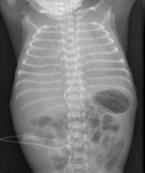

為一種的罕見的疾病,其特征為既往健康的孩子發生急性發作的嚴重休克,腦病和其他癥狀,并導致死亡或極其嚴重的神經系統損害結果。發病迅速,死亡率高,生存者易留有嚴重的神經后遺癥。其特點是突發的昏迷和抽搐、休克、BCD、水樣腹瀉、代謝性酸中毒、肝腎功能障礙。出血性休克和腦病綜合征(HSES)主要發生在3~8個月之間的嬰兒(平均年齡為5個月),但也有報道發生于15歲。